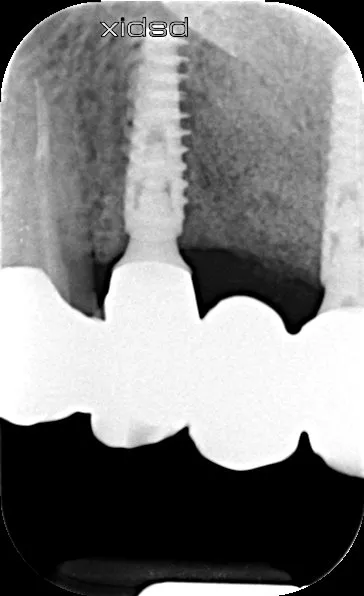

17a-b-c-d. Retro-alveolar X-rays at the end of treatment. Note bone behavior around the 4 implant collars. Soft tissue height above each collar was 3 to 4 mm.